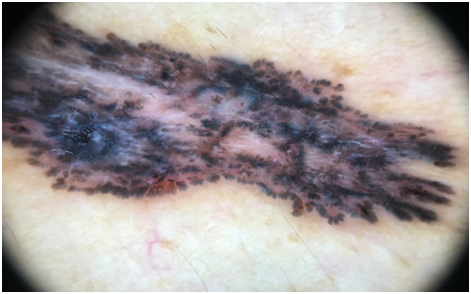

An 80years old male patient presented to our department with a gradually progressive asymptomatic dark colored lesion at the site of black tattoo ink used for marking skin for directing the radiotherapy beam for adenocarcinoma prostate 12years before. His past medical and surgical history included: multiple treated malignancies in last 35 years in the form of Non Hodgkins lymphoma occurred in 1983 treated with CHOP (cyclophosphamide, doxorubicin, vincristine, and prednisone) regimen and radiotherapy, adenocarcinoma of the stomach in 1996 and adenocarcinoma of the rectum in 2003, which were managed with chemotherapy and surgical resection. In 2006 the patient developed an adenocarcinoma of the prostate managed with chemotherapy and radiotherapy. No family history of multiple malignancies was present in parents, siblings or children. Examination revealed a solitary well defined black colored plaque measuring 05cm x 02cm at 11 o’ clock position from umbilicus in umbilical region not associated with any tenderness or overlying ulceration (Figure 1). Dermoscopic examination revealed leaf like areas at the periphery of the lesion, blue grey ovoid nests, absence of pigment network and specks of black and brown pigment (Figure 2). An incisional biopsy was done from the lesion in view of dermoscopic pattern favoring basal cell carcinoma. Histopathology revealed stratified squamous epithelial lining with irregular proliferation of tumour from undersurface of epidermis and extending into dermis (Figure 3). Tumour nests comprised of basaloid cells with peripheral palisading showing mild pleomorphism with high nucleocytoplsmic ratio. Retraction artefact was seen (Figure 4). There was no lymphovascular or perineural invasion. Immunohistochemistry revealed BerEP4 positivity with no loss of BCl2, negative for epithelial membrane antigen and Carcinoembryonic antigen. Histopathological findings were consistent with Basal cell carcinoma. Patient was managed with wide surgical excision of tumour with 05mm margins and post operative histopathology specimen showed all margins free of tumour. Patient is on regular follow up for any recurrence of Basal cell carcinoma at the same or any other site and also other malignancies.

Figure 2 Leaf like areas at the periphery of the lesion, blue grey ovoid nests, absence of pigment network and specks of black and brown pigment.